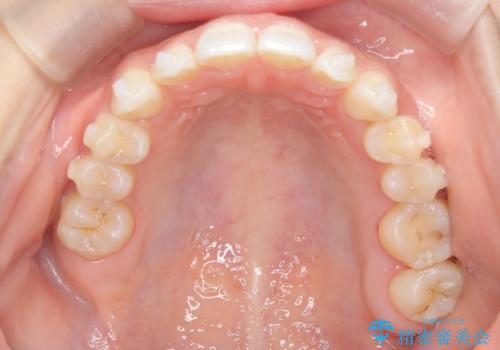

- 空隙歯列を主訴に来院された患者様です。

ばらけている空隙を一箇所に集めながら咬合や正中を改善して最後に補綴治療を行なっています。

右上の臼歯クロスバイトは骨格生のため、そのままにしています。